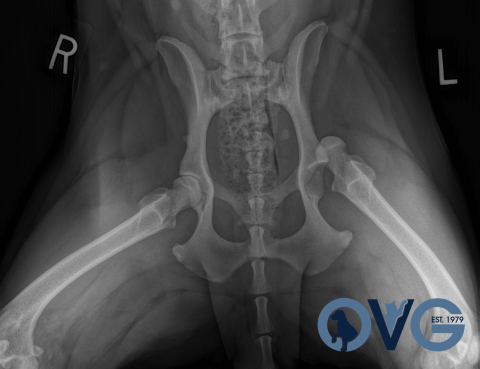

Post Operative Radiographic Examination Ven Trodorsal View